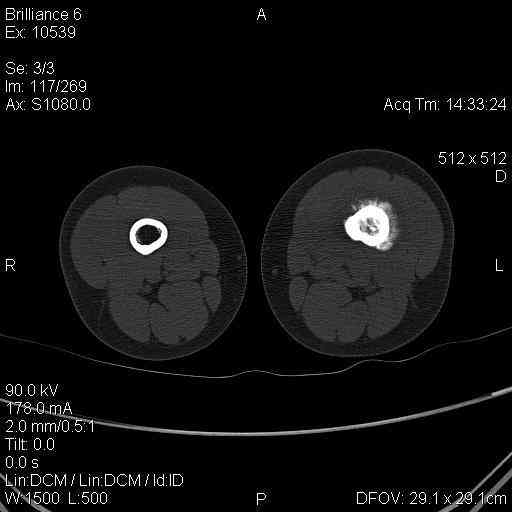

Мальчик 8 лет. Жалобы на боли в левом бедре. Со слов мальчика, ударился бедром несколько

недель назад, после чего и начались боли.

В общем-то, диагноз сомнения не вызывает злокачественная опухоль, вероятнее всего -

остеогенная саркома. У нас возникла дискуссия по поводу того, нужно ли брать открытую

биопсию для гистологического подтверждения диагноза, либо сразу направить ребёнка в

специализированный центр. С одной стороны, диагноз должен быть подтверждён

гистологически. С другой - каждое нерадикальное вмешетельство на опухоли увеличивает

вероятность метастазирования. В литературе чаще встречается такой подход - пациента сразу

направляют в специализированный центр, где ему проводят как биопсию, так и дальнейшее

лечение. Хотелось бы узнать мнение уважаемых коллег.